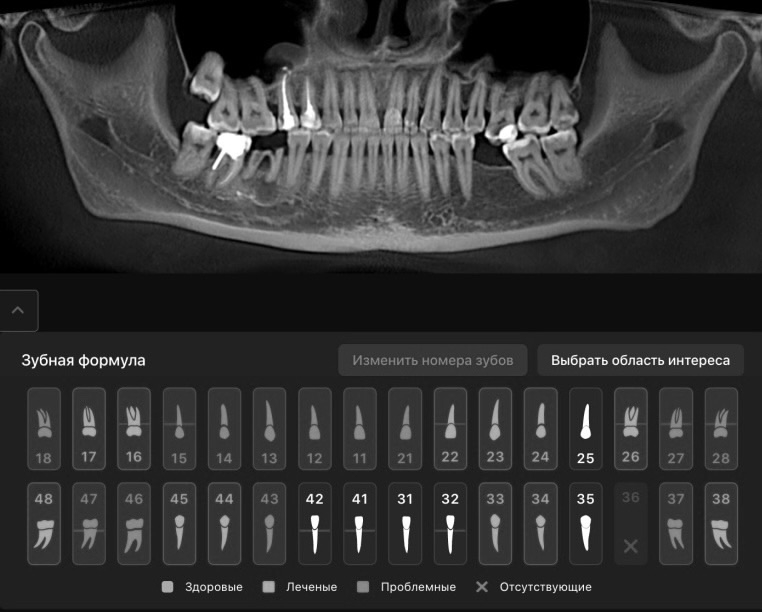

Полный отчет по состоянию полости рта от искусственного интеллекта - бесплатно!

Услуга доступна для всех пациентов клиники Dental Palace